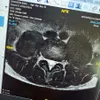

"Gue pikir karena faktor U (usia), ternyata emang cedera pinggangnya. Jadi gue kena HNP di L3, L4, L5 sama S1," jelas Ganindra Bimo dalam unggahan Instagram, hari Selasa (19/8).